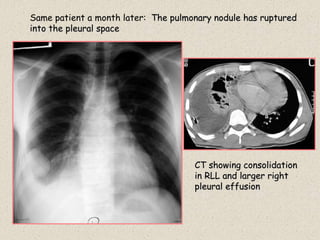

History: Young Greek patient with a cough

Case 22

Same patient three weeks later

Right lower lobe pulmonary nodule cavitates

Same patient a month later: The pulmonary nodule has ruptured

into the pleural space

CT showing consolidation

in RLL and larger right

pleural effusion